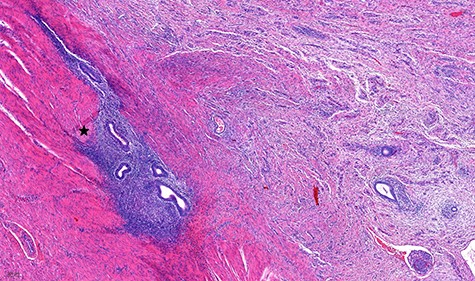

The histological exam showed an ileocolic intussusception because of extended perimural adhesions in the range of severe local extended endometriosis with several foci in the lamina propria of the colon layer and in the fibrotic zone (Fig. 5).

Histological specimen of the endometriosis (scale 200 μm). In detail the outer layer of the muscular bowel wall and adjacent subserosal tissue with fibrosis; embedded there are islands of inconspicuous endometrial-type glands and stroma (black star) with banal cytology.